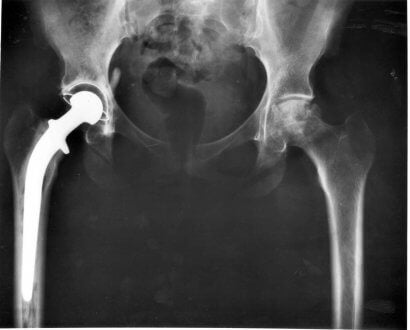

Entre as operações cirúrgicas que os veterinários podem realizar, há a substituição total ou parcial do quadril.